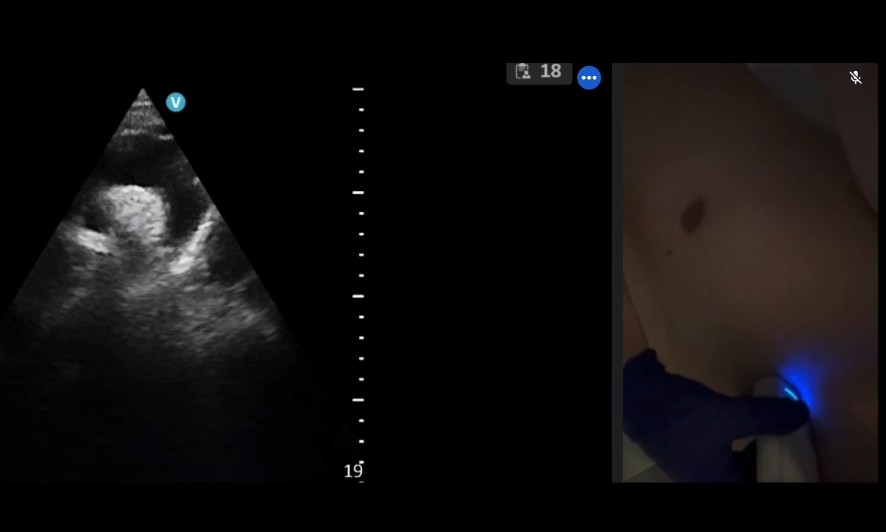

RECURSOS DIDÁCTICOS Inicio » RECURSOS DIDÁCTICOS Videos Documentos Publicaciones Casos clínicos VIDEOS Ver más DOCUMENTOS Checklist muerte encefálica Protocolos de diagnóstico y certificación de la muerte encefálica VSCAN-STROKE: evaluación ultrasonográfica con VSCAN de fuentes embolígenas cardioaórticas por un neurólogo en la fase hiperaguda del ictus isquémico Recomendaciones SONES para realizar estudios ecográficos durante la pandemia SARS-CoV-2 (COVID-19) Impacto de la pandemia covid19 en los laboratorios de neurosonologia Ver más PUBLICACIONES Estado de la neurosonología en España. Un estudio de la Sociedad Española de Neurosonología (SONES). J. Rodríguez-Pardo , J. Carneado-Ruiz, M. Martínez-Martínez, J.M. Moltó-Jordá, P. Irimia, J. Serena-Leal, Ó. Ayo-Martín, P. Martínez Sánchez, J. Pagola J. Fernández-Domínguez Supraesternal aortic debería salir del modo siguiente: Suprasternal aortic arch echocardioscopy as a potential tool in detection and follow-up of mobile thrombi in patients with ischemic stroke. Esnaola Barriola I, Escriche Gorospe E, Miguel Navas P, Martínez Campos E, Molina Goicoechea M, Capell Pascual F, Jiménez Delgado A and Muñoz Arrondo R (2025) Documento de consenso sobre técnicas neurosonológicas en cefaleas. J. Rodríguez Vico, J. Fernández Domínguez, F.J. Julián Villaverde, N. González García, C. García-Cabo Fernández, A. Jaimes Sanchez, O. Ayo Martín, J.A. Membrilla López, R.G. Martínez Martín, J. García Ull, P. Martínez Sánchez, L. Dorado Bouix, R. Belvis Nieto, P. Irimia.Neurología, 2024. Point-of-care ultrasound for transient ischemic attack assessment in transient ischemic attack clinics: Consensus document of the Spanish Society of Neurosonology. Amaya-Pascasio, L., Rodríguez-Pardo de Donlebún, J., Arjona-Padillo, A., Fernández-Domínguez, J., Martínez-Martínez, M., Muñoz-Arrondo, R., García-Sánchez, J. M., Pagola Pérez de la Blanca, J., Carneado-Ruiz, J., & Martínez-Sánchez, P. Neurología. 2024 Increased vertebral canal diameter measured by ultrasonography as a sign of vasculitis in patients with giant cell arteritis. Ayo-Martín O, Segura T et al. Frontiers in Medicine 2023 Transcranial sonography in atypical parkinsonism: how reliable is it in real clinical practice? A multicentre comprehensive study. Alonso Cánovas A, Tembl Ferrairó JI, Martínez-Torres I, López-Sendón Moreno JL, Paree-Moreno I, Monreal-Laguillo E et al. Parkinsonism related disorders 2019; 68: 40-45 Qué debería saber el médico de familia sobre la ecografía transcraneal en neurología. Fernández Domínguez J. FMC 2016; 23 (8): 467-473 Evaluación de la sustancia negra mediante ultrasonografía transcraneal. Vivó-Orti M, Tembl JI, Sastre-Bataller I, Vázquez-Costa JF, Sahuquillo P, Burguera JA. Rev Neurol 2013; 56 (5): 268-274 Utilidad del duplex orbitario para la valoración de atrofia del nervio óptico en enfermedades desmielinizantes: estudio piloto. Fernández-Domínguez J, García-Rodríguez R, Mateos V. Rev Neurol 2012; 54 (10): 587-592 Dúplex transcraneal en la enfermedad de moyamoya. Vázquez-Sánchez F, López-Veloso M, Argandoña-Palacios L, Segura T. Rev Neurol 2012; 54 (2): 249-250 Ver más CASOS CLÍNICOS Caso 7 – 2023 Ver caso Ver todos los casos SONES SOCIEDAD ESPAÑOLADE NEUROSONOLOGÍA secretariasones@gmail.com HAZTE SOCIO ¡Síguenos en Twitter!